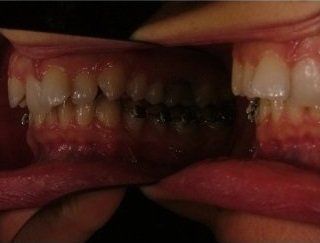

L'idea innovativa di applicare delle maniglie (brackets) sul lato interno dei denti, rivolto alla lingua anziché sul lato esterno rivolto al labbro ed esposto al sorriso, ha fatto sì che questa tecnica venisse denominata “linguale".